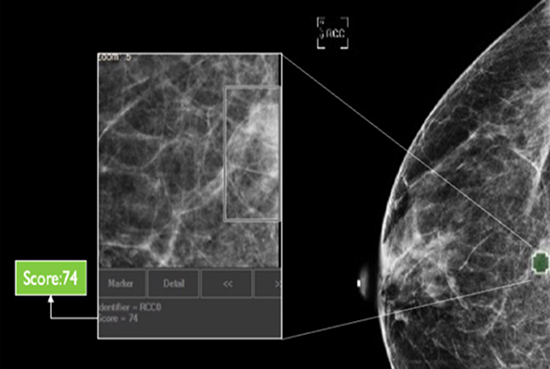

cmAssist has the ability to quickly detect key regions of interest on a mammogram, and accurately quantify and label anomalies as suspicious or, instead, verifiably benign. cmAssist does this by searching all the views of a digital 2D-mammogram for abnormal areas of density, mass or calcification and by highlighting suspicious areas requiring further analysis. Once anomalies are flagged in the system, cmAssist then marks the mammogram and highlights the identified anomalies.

The software also generates a unique, data-driven neuScore™ that provides radiologists with a quantitative measure of suspiciousness in a marked region of interest, ranging from 0 (least suspicious) to 100 (highly suspicious). This score can be tracked over time to evaluate the stability or evolution of identified anomalies.